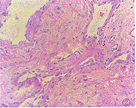

心臟粘液瘤腫瘤大小不一,多有蒂與心房或心室壁相連,外形多樣,外觀富有光澤,呈半透明膠凍狀。切面呈實質性,間有斑片狀出血區及充滿凝血塊的小囊腔。顯微鏡下可見腫瘤細胞呈星芒狀、梭形、圓形或不規則形,散在或呈閉索狀分布於大量粘液樣基質中,胞核多為單核也可呈多核瘤巨細胞。粘液肉瘤瘤細胞形態不一,胞核大,染色深,可見核分裂,瘤細胞可浸潤至小血管內形成瘤栓。